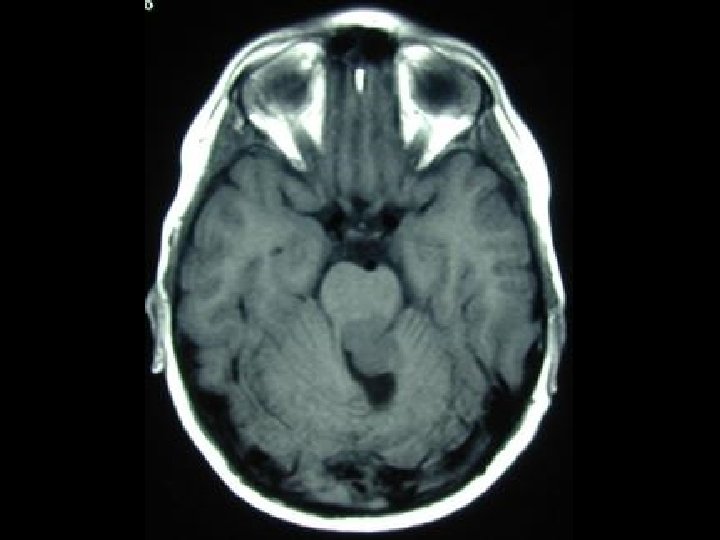

Mozečková ataxie ataxická chůze a postoj nádor mozečku vlevo • ve stoje padání doprava • pevný stoje na pravé noze • vratký stoj na levé noze • ataktická chůze